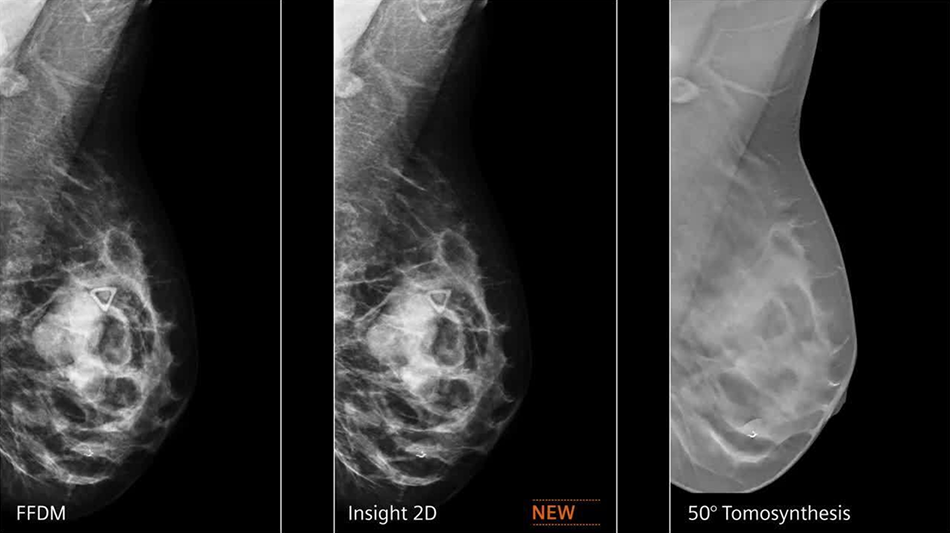

Digital breast tomosynthesis (DBT) is an advanced form of mammography that captures multiple low-dose X-ray images of the breast from different angles. These slices are reconstructed into a 3D image, providing a clearer view of internal structures compared to traditional 2D mammograms.

This 3D imaging approach minimizes the issue of tissue overlap, which often obscures small tumors or lesions in 2D scans. DBT significantly improves cancer detection rates, particularly in women with dense breast tissue.